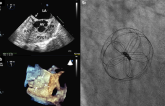

Comparison of Residual Shunt Rate and Complications: 6 Different PFO Closure Devices

October 30, 2019